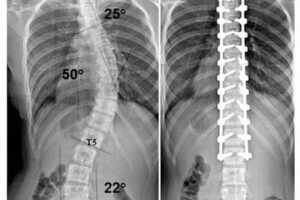

Рентген или МРТ — принципиальные отличия и особенности проведения

Вопрос о вредности рентгеновских лучей или магнитно-резонансной томографии важен для пациентов, которые сталкиваются с выбором инструментальной дифференциальной диагностики. Та или иная процедура должна соответствовать диагностическим целям. Рентген и МРТ назначают для оценки состояния внутренних органов, определения опухолевидных новообразований и целостности тканей. Оба метода имеют принципиальные отличия и рекомендуются при проявлении диагнозов и болезненных состояний человека. …